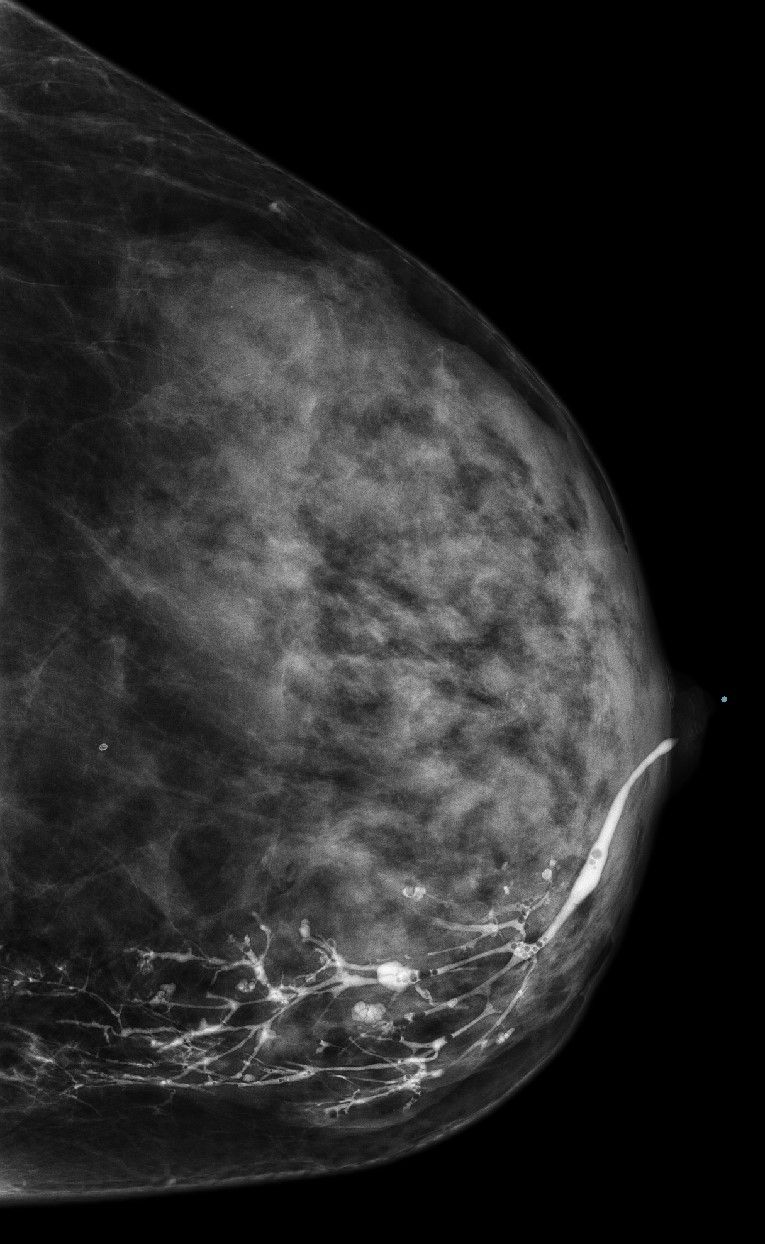

Galaktographie zur Darstellung der Milchgänge

Die

Galaktographie ist eine spezielle Untersuchungsmethode in der komplementären Mammadiagnostik, bei der ein Kontrastmittel in einen Milchgang der Brustdrüse gespritzt wird. Anschließend wird die Brustdrüse mittels Röntgenstrahlen in verschiedenen Ebenen abgebildet. Die Galaktographie wird vor allem bei Frauen mit einer Absonderung aus der Brustwarze eingesetzt. Durch die Galaktographie können Veränderungen in den Milchgängen erkannt werden.